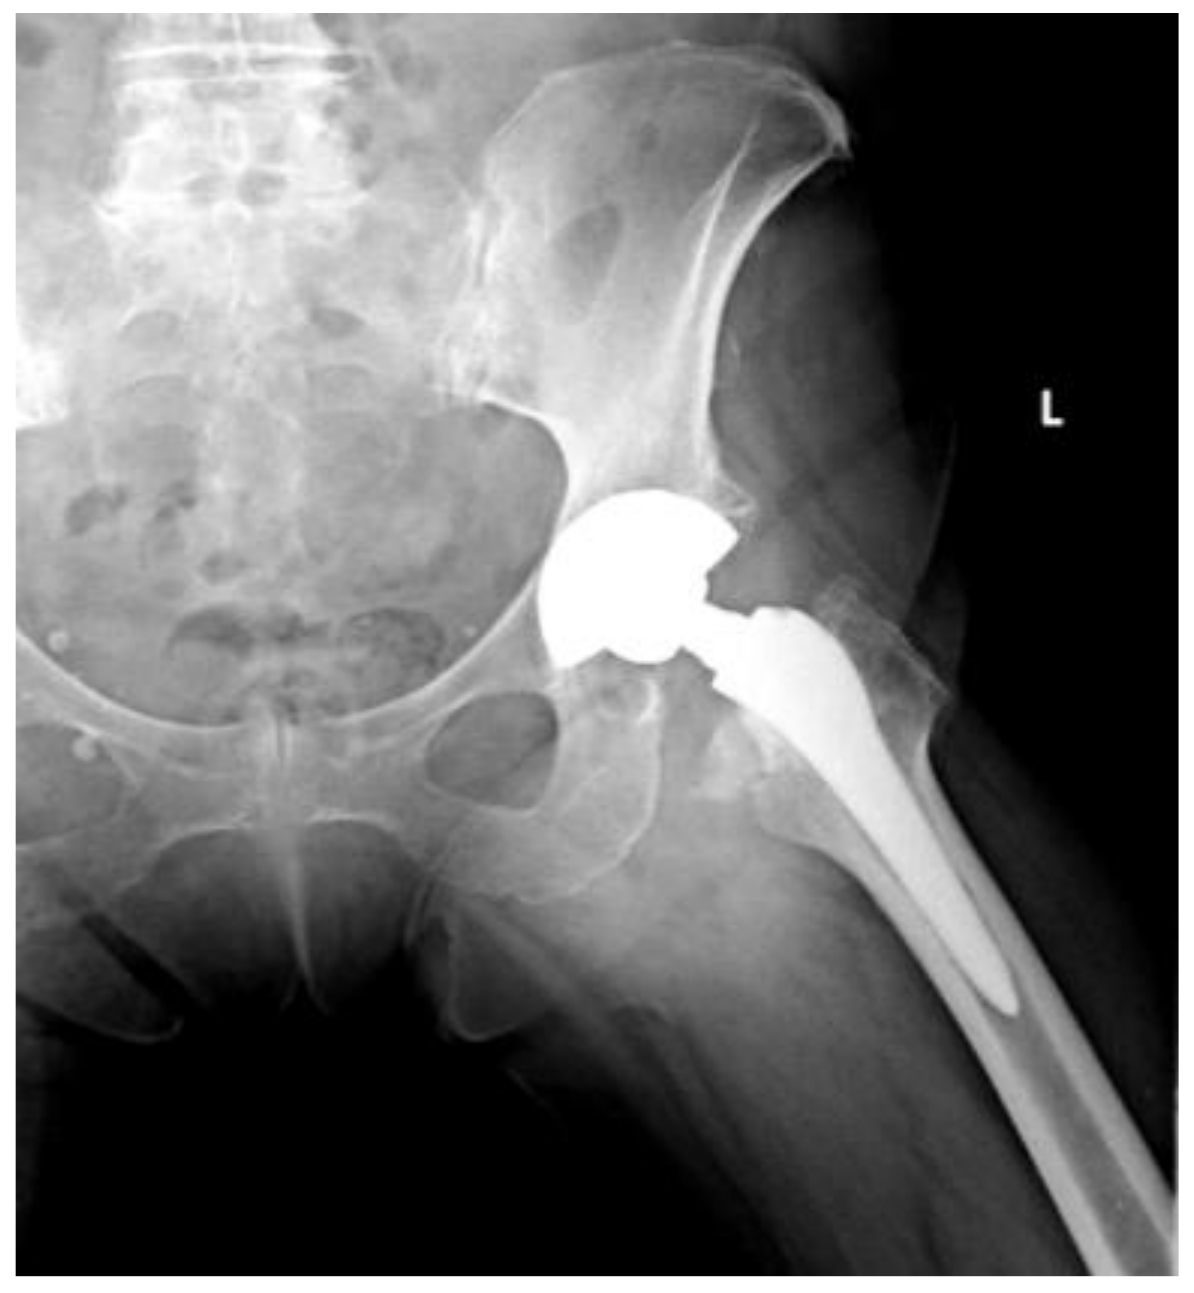

Of the 84 patients enrolled in this study, 44 patients (52.4%) received a THA with a straight stem (group A) (Figure 1 and Figure 2) and 40 patients (47.6%) received a THA with an anatomical stem (group B) (Figure 3 and Figure 4).

Figure 2.

Axial X-rays view of a total hip arthroplasty with straight stem (group A).